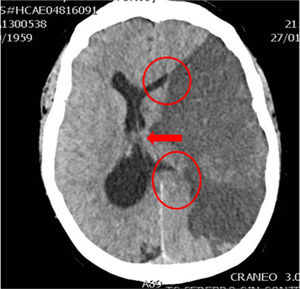

En la práctica clínica, antes de establecer un pronóstico definitivo, se recomienda la opinión de un equipo multidisciplinar experto, que minimice el sesgo personal; en esta valoración el especialista en Medicina Intensiva, por sus conocimientos sobre la enfermedad neurocrítica, juega un papel primordial. La lesión cerebral catastrófica condiciona una elevada presión intracraneal (PIC), con una disminución de la presión de perfusión cerebral e instauración progresiva de la parada circulatoria cerebral. La probabilidad de evolucionar a ME ha de sustentarse en datos clínicos, de neuromonitorización y resultados de la tomografía computarizada (TC) craneal. En primer lugar, hay que tener en cuenta la situación clínica neurológica, medida por las escalas habituales de gravedad según las diferentes enfermedades (escalas de Glasgow [GCS], Hunt y Hess, NIHSS), así como la ausencia de algunos reflejos de tronco del encéfalo. Las escalas de gravedad realizadas en las primeras horas de la lesión tienen sus limitaciones y su valor pronóstico mejora cuando se realizan después de la reanimación del paciente. La probabilidad de error pronóstico es siempre menor cuando estas escalas tienen un valor extremo; a mayor gravedad clínica, mayor probabilidad de evolución a ME37. En este sentido, algunos estudios encuentran que la abolición de 3 reflejos de tronco al ingreso es la variable que más predice la evolución a ME38. Otro de los factores pronósticos que pueden ayudar a predecir una alta probabilidad de evolución a ME es la TC craneal, ya que permite documentar el tipo, el volumen, la localización y la gravedad de la lesión estructural, así como la existencia de signos de hipertensión intracraneal y herniación cerebral. En las hemorragias cerebrales, el volumen del hematoma es uno de los predictores más potentes de evolución a ME y algunos autores encuentran que un volumen superior a 65cc es un factor determinante39. Igualmente, la presencia del «signo del remolino» en la TC sin contraste y del spot sign en la angio-TC nos indica que hay presencia de sangrado activo por arteriolas o vénulas y es un signo de mal pronóstico que algunos autores asocian con una mayor probabilidad de evolución a ME38,40,41. El desplazamiento de la línea media nos informa del grado de compresión y es un indicador, junto con el estado de las cisternas de la base, del compromiso de las estructuras encefálicas. El borramiento parcial o total de las cisternas de la base es un fuerte indicador de probable evolución a ME42. La presencia de signos de herniación cerebral en la TC implica hipertensión intracraneal y, por lo tanto, riesgo elevado de enclavamiento cerebral. Los 3 tipos más frecuentes de herniación cerebral son: herniación subfalcial, que se caracteriza por un desplazamiento de la línea media y compresión del ventrículo lateral ipsilateral (fig. 1), la herniación uncal o transtentorial, donde existe una dilatación de la cisterna del ángulo pontocerebeloso ipsilateral y del cuerno temporal del ventrículo lateral contralateral (fig. 2), y la herniación amigdalina, que se caracteriza por la desaparición de la cisterna magna y el descenso de las amígdalas cerebelosas por debajo de la línea de Chamberlain. La vaina del nervio óptico se continúa con las meninges del sistema nervioso central y acumula líquido cefalorraquídeo en este espacio subaracnoideo, aumentando su diámetro cuando hay un incremento de la PIC. Su diámetro se puede medir por ultrasonidos, resonancia magnética y TC craneal, y aunque no existe unanimidad sobre el lugar de la medición ni el diámetro necesario para considerar hipertensión intracraneal, algunos autores confirman que un diámetro de la vaina del nervio óptico>5-6mm tiene una fuerte correlación con una PIC superior a 20mmHg43,44.

Herniación uncal o transtentorial. A: colapso del asta temporal y de la cisterna ambiens ipsilateral a la lesión expansiva (flecha). Dilatación del asta temporal contralateral (círculo). B: dilatación de la cisterna cerebelopontina ipsilateral (flecha). (Cortesía de Ángela Meilán, Servicio de Radiología del Hospital Universitario Central de Asturias).